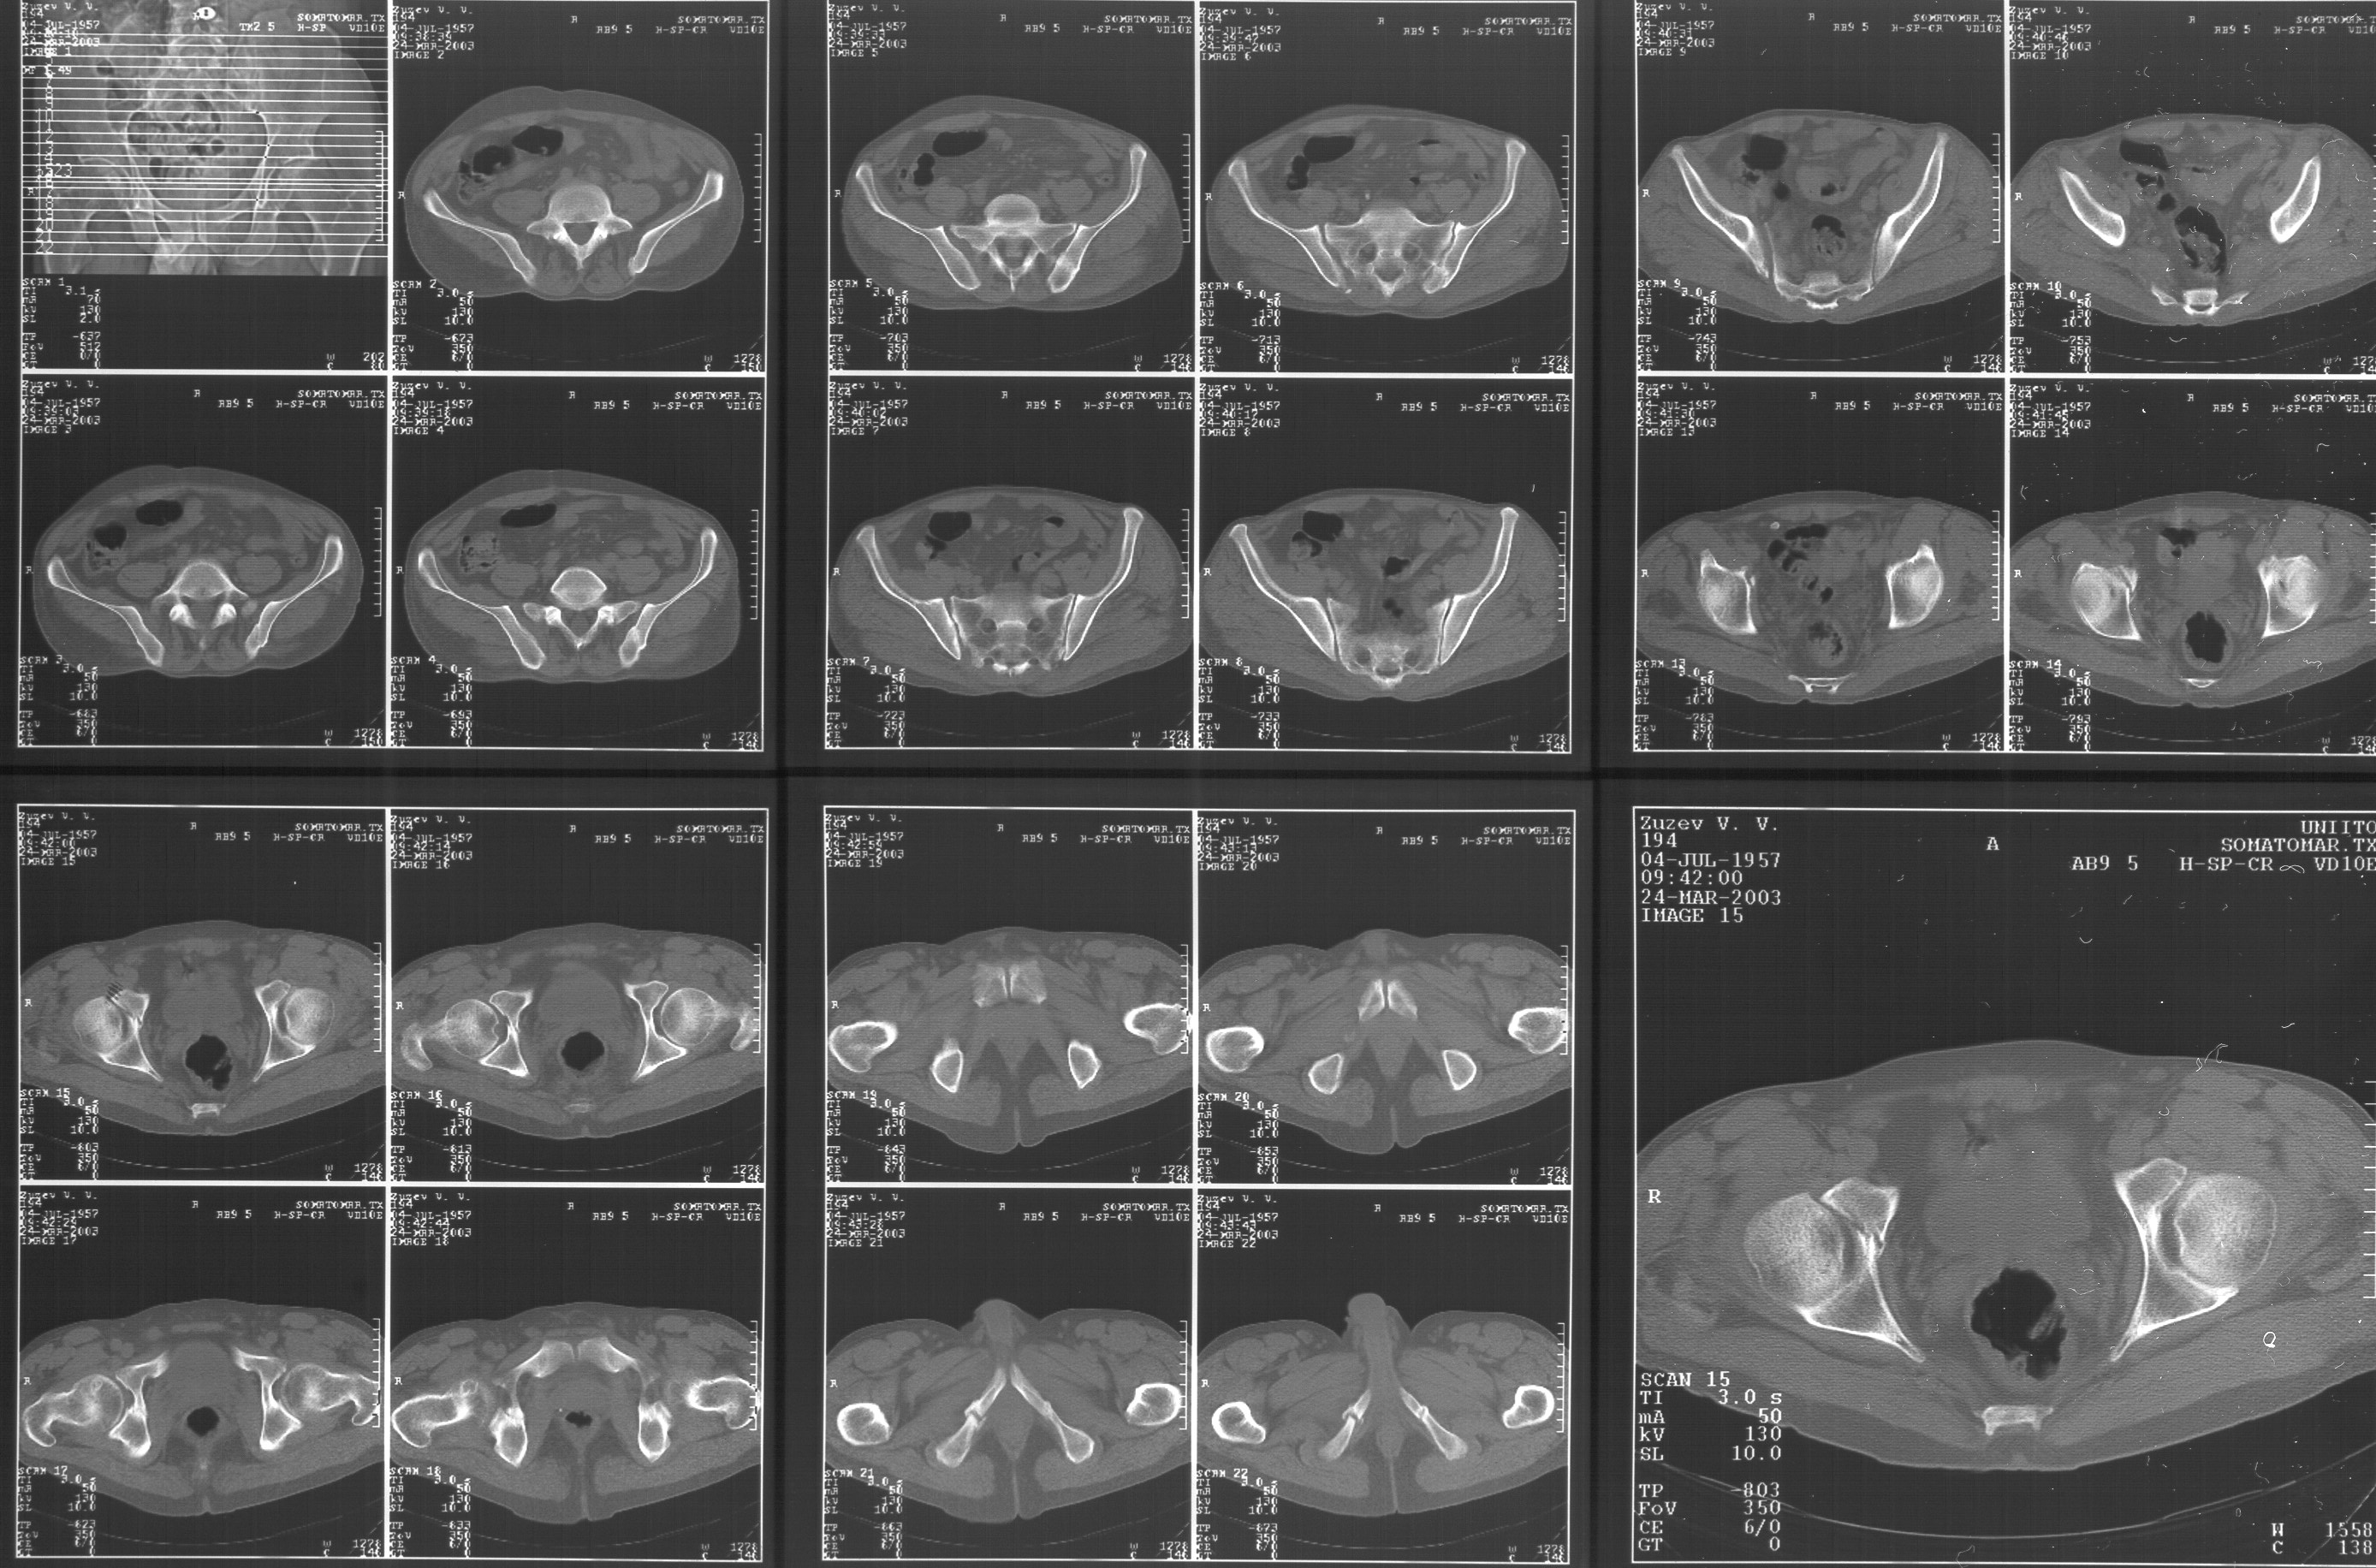

Прилагаю свежую КТ таза.

Картинки см. ниже, левая - с экранным разрешением, вторая - полноразмерная, ~900 кб.

КТ в экранном разрешении

Полноразмрная картинка, около 900 кб

Based on the CT images you provided, he appears to have a nonunion of the the right ischium, which would explain his symptoms. General principles of treatment of hypertrophic (which this appears to be) nonunions suggest rigid fixation, but I'm not sure what the best approach would be. Could get a lag screw across the fracture through a Kocher-Langenbeck approach or plate osteosynthesis through direct ischial approach, but perhaps Chip, Adam or someone with more pelvic fracture experience could enlighten us all.

I think the CT cuts in question are on the right of the bottom row i.e.

http://www.hwbf.org/hwb/conf/alex47/image3a.jpg

Thanks for the link to the plain films and CT images.

I think this is just a pelvic ring disruption that has gone on to a non-union. The arrow is pointing to the inferior ramus non-union, and

the sup ramus is a high "root" fracture, right near the pecten. The sup ramus fracture enters the tab - you could call it an acetabular

fracture - but down here in Dallas we treat these acutely as stable pelvic ring injuries. The fracture in the anterior portion of the

acetabulum is so low it doesn't seem to cause much trouble.

His R sacroiliac joint is opened anteriorly a little bit - the "unreduced posterior lesion" Alex mentioned in his first post. My earlier post about plating, bone grafting, etc., is all wrong.

What you have is a pelvic fracture that hasn't healed after 4 months or so, with a minimal deformity.

I think what I would offer the guy is a percutaneous iliosacral screw to stabilize and improve the SI joint alignment, coupled with a perc anterior column screw to stabilize the high ramus fx. These screws aren't easy to place, and have a host of potential problems and complications. But, I think they would work.

Как Вы сами видели на томограммах, грубых деструктивных явлений крестцово-подвздошного сочленения не определяется( маркировка правая -левая сторона не видна), определяется сравнительно незначительное расширение суставной щели с одной стороны и не более того.

Виноват, первый раз не обратил внимания на возможность полноформатного просмотра томограмм. В этой связи -дополнения к своему первому комментарию: сросшийся перелом вертлужной впадины справа, L5-S1 спондилоартроз, расширение суставной щели крестцово-подвдзошного сочленения справа может компрометировать его стабильность и вызывать локальные боли, но вряд ли это может давать двусторонние проявления в нижних конечностях. Все-таки миелограмма или ЯМР желательно иметь, чтобы определиться в тактике.

Я в некотором присоединяюсь к Коллеге из Далласа:

Речь идёт о коплексном двустороннем повреждении таза с нарушением тазового кольца.

А именно: разрыв илио-сакрального сочленения справа, на этой же стороне трансацетабулярный перелом с незначительным смещением, перелом подвздошной кости слева. Исходя из вышеперечисленного, меня не удивляют двусторонние жалобы пациента. Однако, учитывая представленные снимки ЯМР и времени, прошедшим с момента травмы мне представляется пока преждевременным говорить об образовании ложных суставов. Судя по развиввшейся костной мозоли в области вышеперечисленных очагов, все переломы находяться в стадии консолидации. Вполне возможно, однако, что трансацетабулярный перелом приведёт в дальнейшем к развитию посттравматического артроза ТБ- сустава.